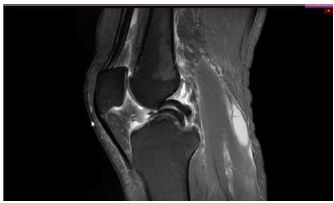

Um paciente de 19 anos de idade sofreu entorse do joelho direito durante agachamento em partida de futebol. Foi retirado do campo e queixando-se de dor na face interna do joelho. Foi levado ao hospital mais próximo e, ao ser examinado, percebeu que não conseguia estender completamente o joelho. Não conseguia flexionar totalmente o joelho também. Notaram-se ainda, edema e o sinal da tecla.

Considere que, no caso clínico descrito, foi realizado o exame complementar, conforme apresentado. Essa figura mostra

Diante do diagnóstico do caso clínico citado, a conduta terapêutica adequada seria